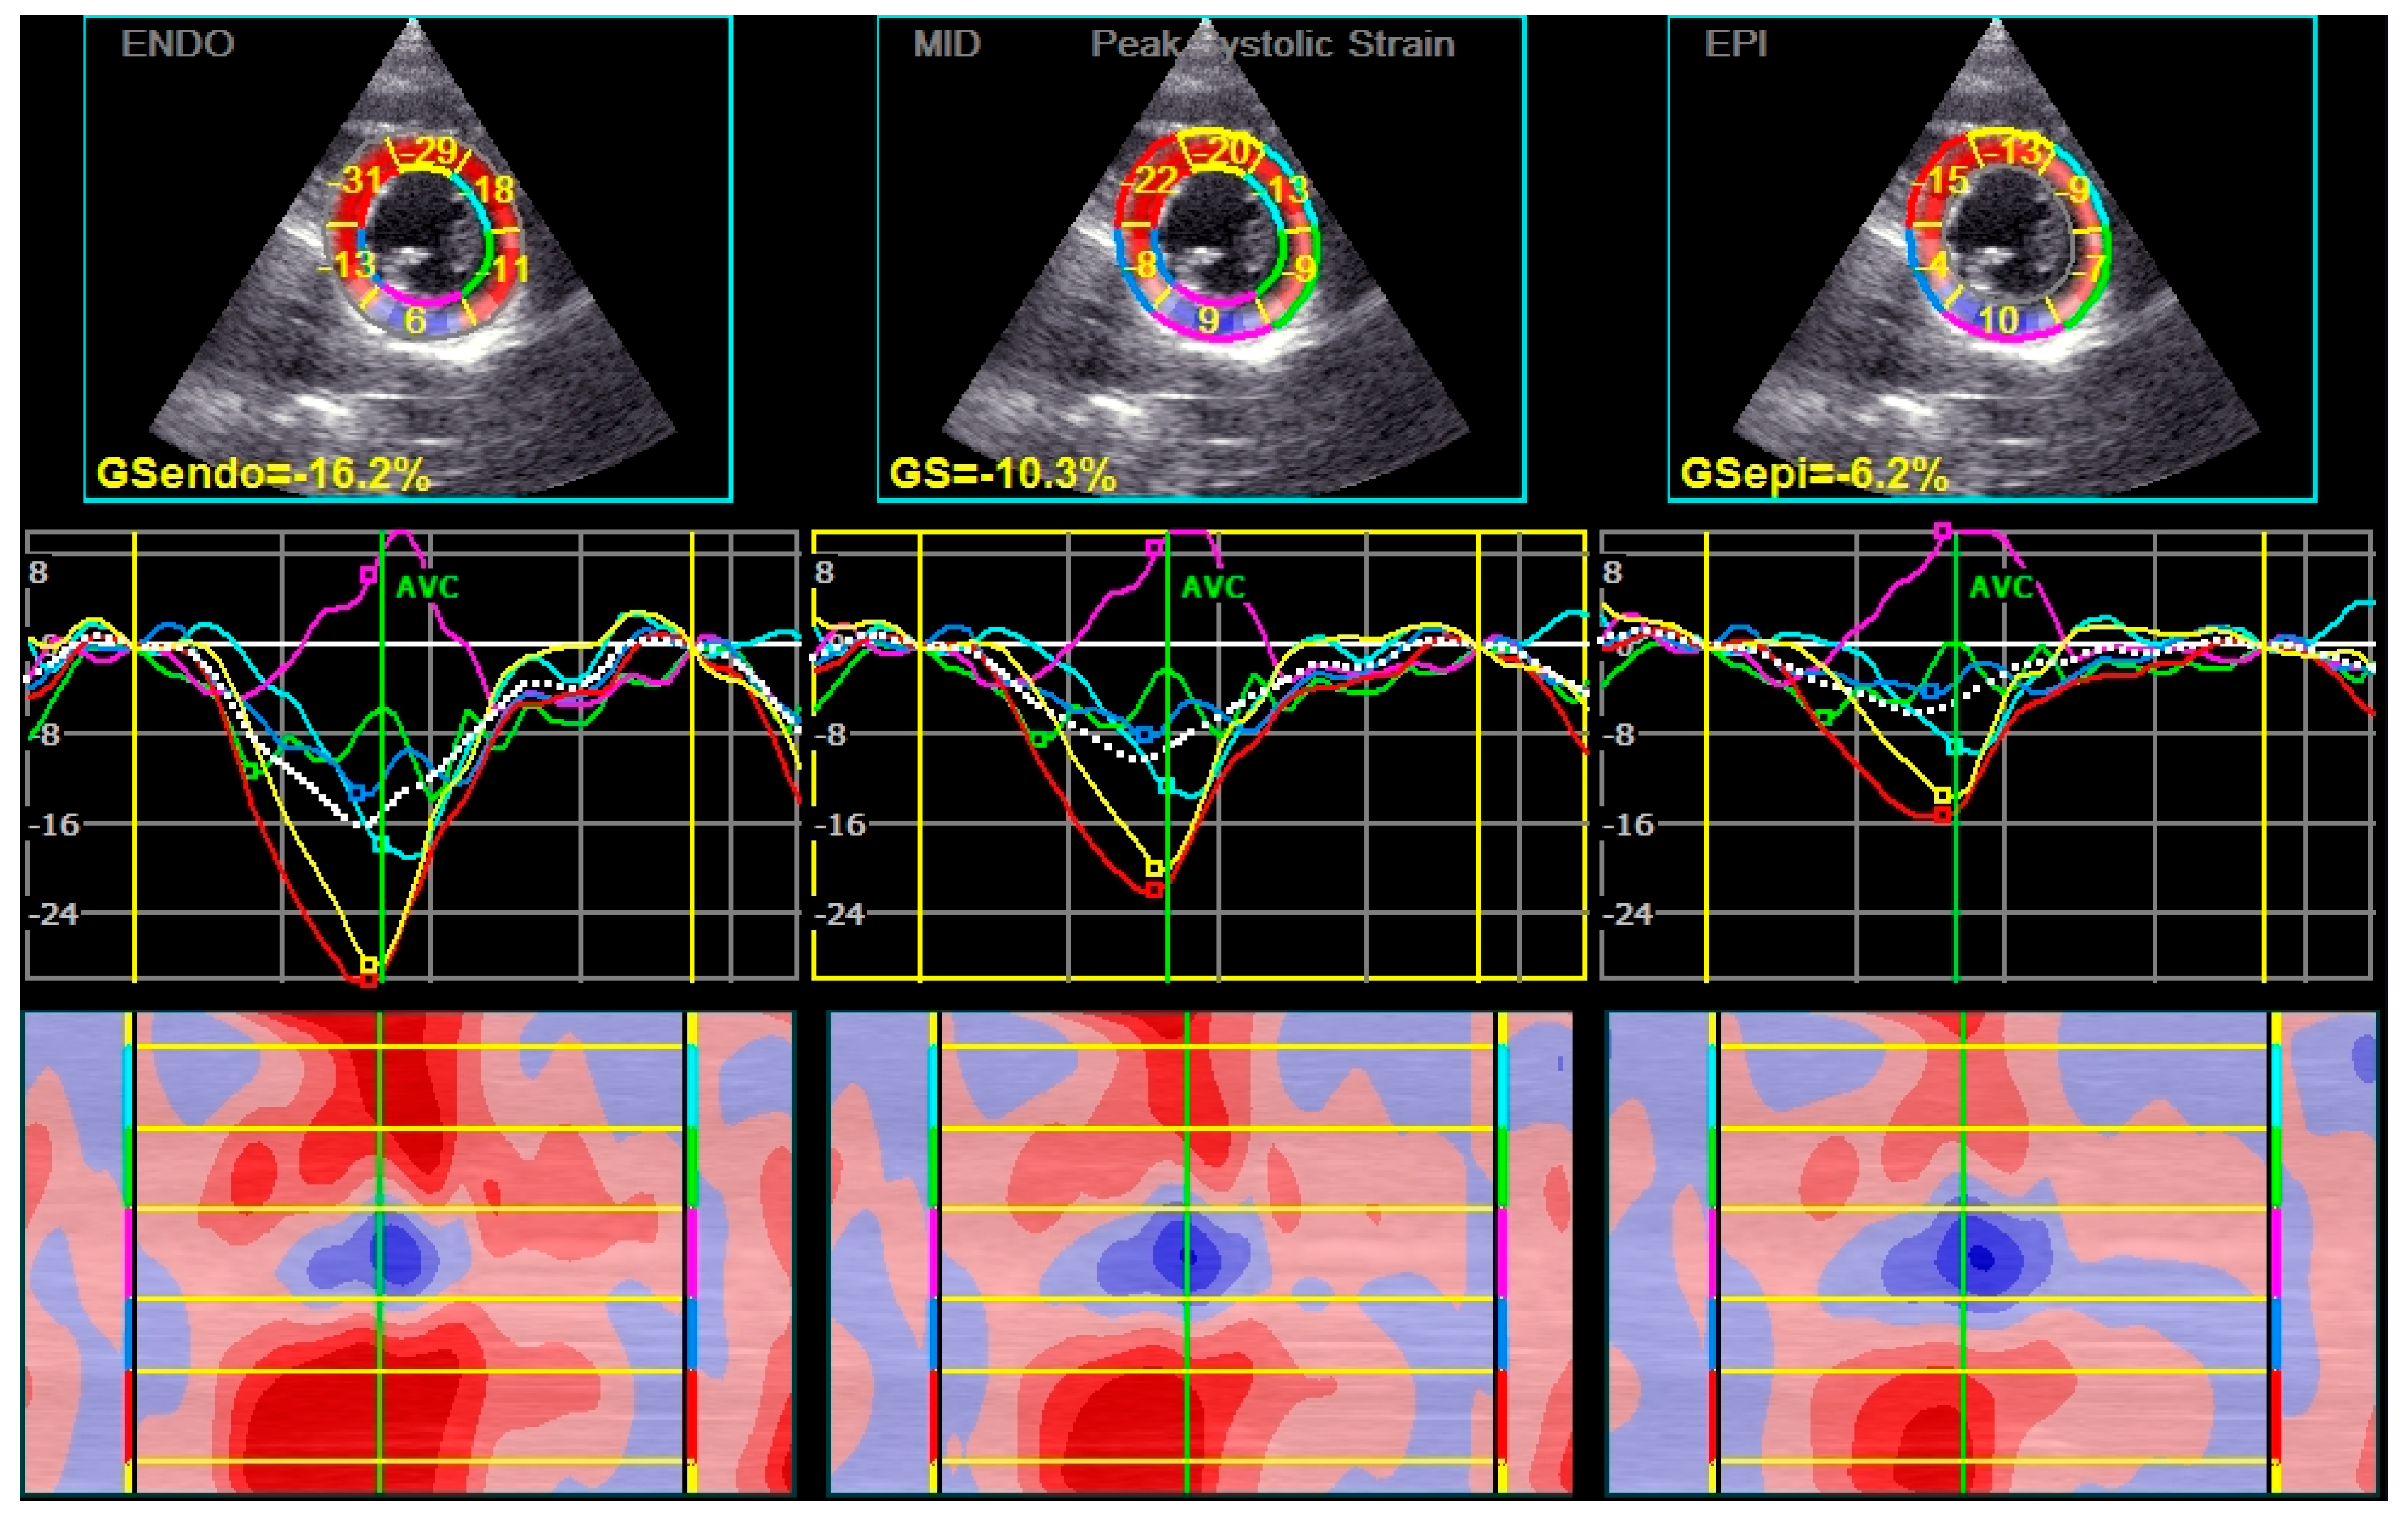

| GLS endo (%) mean ± SD | −21.5 ± 2.9 | −22.5 ± 3.1 | 0.041 |

| GLS mid (%) mean ± SD | −19.1 ± 2.5 | −19.9 ± 2.7 | 0.048 |

| GLS epi (%) mean ± SD | −17.3 ± 2.3 | −17.9 ± 2.4 | 0.064 |

| Peak Systolic LS endo (%) mean ± SD | −20.9 ± 3.1 | −22.0 ± 3.2 | 0.038 |

| Peak Systolic LS mid (%) mean ± SD | −18.6 ± 2.7 | −19.5 ± 2.7 | 0.043 |

| Peak Systolic LS epi (%) mean ± SD | −16.8 ± 2.4 | −17.5 ± 2.5 | 0.056 |